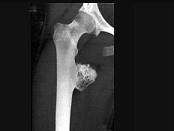

男,36岁,髋关节疼痛、肿胀,活动受限1月,结合图像,最可能的诊断是?(?)A.骨肉瘤B.软骨瘤C.股骨结核D.软骨肉瘤E.转移瘤

问题 男,36岁,髋关节疼痛、肿胀,活动受限1月,结合图像,最可能的诊断是?(?)

选项 A.骨肉瘤 B.软骨瘤 C.股骨结核 D.软骨肉瘤 E.转移瘤

答案 D